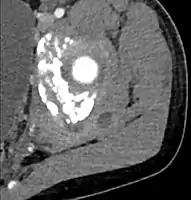

| Transverse T2 magnetic resonance imaging section through the hip region showing abscess collection in a patient with pyomyositis. | |

| Diagnostic method | Diagnostic method used for PM includes ultrasound, CT scan and MRI. Ultrasound can be helpful in showing muscular heterogeneity or a purulent collection but it is not useful during the first stage of the disease. CT scan can confirm the diagnosis before abscesses occur with enlargement of the involved muscles and hypodensity when abscess is present, terogenous attenuation and fluid collection with rim enhancement can be found. MRI is useful to assess PM and determine its localization and extension |